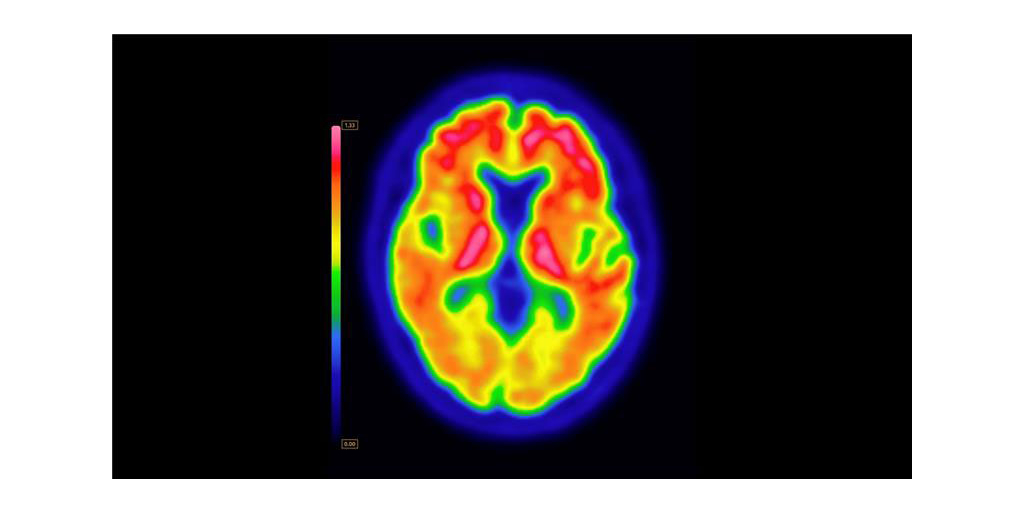

ARLINGTON HEIGHTS, Ill.--(BUSINESS WIRE)--GE HealthCare (Nasdaq: GEHC) today announced that the U.S. Food and Drug Administration (FDA) has approved an updated label for its positron emission tomography (PET) imaging agent VizamylTM (flutemetamol F 18 injection) for beta-amyloid detection. The revised label, effective immediately, expands the indications for use, enables quantitative analysis of Vizamyl scans, and removes significant previous limitations such as monitoring patient response to anti-amyloid therapy.

Up to now, amyloid diagnostics such as Vizamyl have been used to provide a visual assessment of amyloid plaque accumulation in the brain. With quantification now added to the label, clinicians can reach a more objective assessment, using software that enables a calculation of amyloid load, with published research demonstrating that quantification improves diagnostic confidence and consistency among readers1,2,3. In addition, with the removal of a limitation of use for monitoring therapy effectiveness, Vizamyl can also now be used to assess whether the level of amyloid plaques has been reduced sufficiently for the therapy to potentially be stopped.